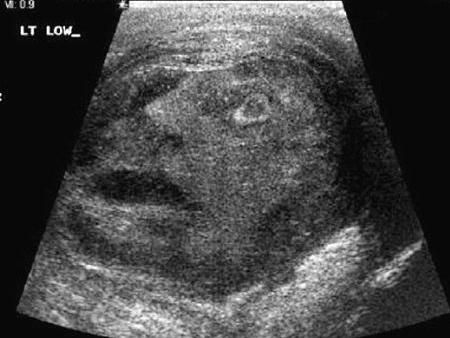

? 【byb.cn】(來源:新浪科技)?新浪科技訊 北京時間11月5日消息,據(jù)國外媒體報道,從火星上的山脈到薄烤餅,我們都曾看到人臉圖案。這一次,加拿大安大略省的兩位科學(xué)家又在睪丸腫瘤中拍到令他們吃驚的人臉,臉上表情痛苦,嘴巴張開。據(jù)悉,這個可怕的人臉圖案是在對一名45歲的睪丸腫瘤患者進(jìn)行超聲波檢查時拍到的。一幅超聲波圖像,人臉圖案清晰可見。

這張臉表情痛苦,右側(cè)的眼睛睜大,嘴巴張開

拍到睪丸腫瘤人臉后,安大略省皇后大學(xué)的格雷格-羅伯茨博士和納吉-杜瑪博士將這幅令人吃驚的圖像遞交《泌尿?qū)W》雜志。9月,《泌尿?qū)W》雜志接受了這幅圖像,作為一個特殊病例的圖片說明,取名為“睪丸疼痛之臉”。羅伯茨和杜瑪表示:“在圖像中看到這個男性面部圖案,醫(yī)生和其他工作人員都感到非常吃驚。這幅圖像是在進(jìn)行超聲波檢查時拍攝的。臉上的表情很痛苦,嘴巴張開,似乎得了睪丸附睪炎?!?/p>

他們指出人臉圖案并不是神靈發(fā)出的信號,例如埃及神話中掌握男性生育的神“Min”,而只是一種巧合。當(dāng)時,兩位醫(yī)生測量這位患者的一種水平升高的激素(通常說明患上癌癥)?;颊咦詈鬀Q定切除睪丸,因為這是能夠得到確診的唯一方式。不幸的是,檢查結(jié)果顯示腫瘤屬于良性。